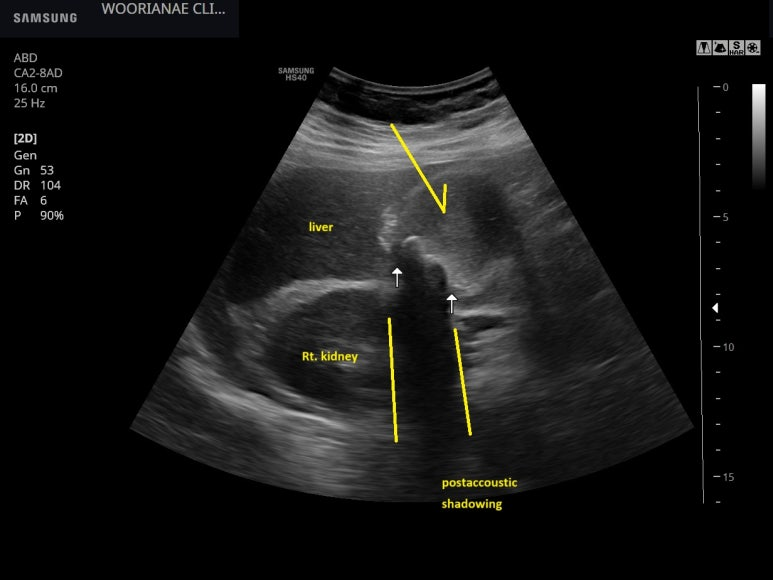

transverse view, 화살표가 내용물로 꽉찬 음영

--> 담석 및 담낭 수종 (gallbladder hydrops)